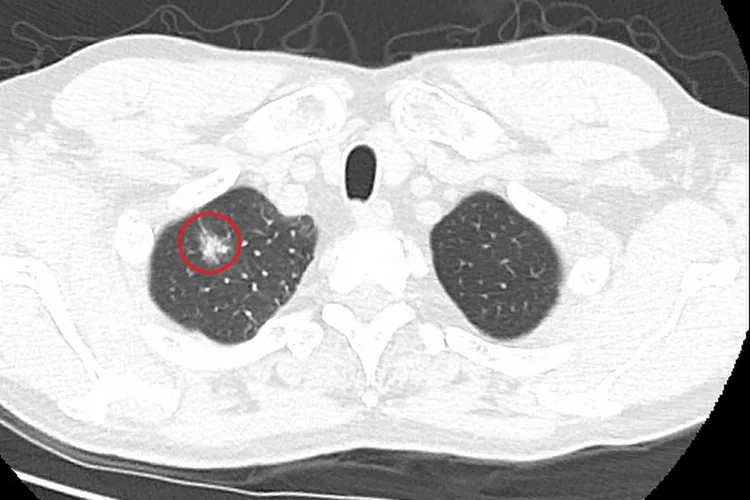

肺癌蟬聯43年國人十大癌症死因第一位,洪嘉聰表示,「低劑量電腦斷層篩檢」(LDCT)是目前唯一具國際認證,可以早期發現肺癌的篩檢工具,建議具肺癌家族史的50-74歲男性或45-74歲女性,以及50-74歲具重度吸菸史的民眾,每兩年接受一次公費篩檢,以達到早期診斷、早期治療。

國健署統計,台灣每年新診斷的肺癌超過1.5萬人,其中肺腺癌占比高達70%至80%。台北慈濟胸腔外科醫師洪嘉聰說明,早期肺腺癌多無症狀,X光檢查大多無法發現,通常有症狀時多半已經第三、四期。常見症狀包含胸悶胸痛、呼吸喘、體重減輕等,若出現遠端器官轉移,也可能有腦神經學症狀或骨頭痛。